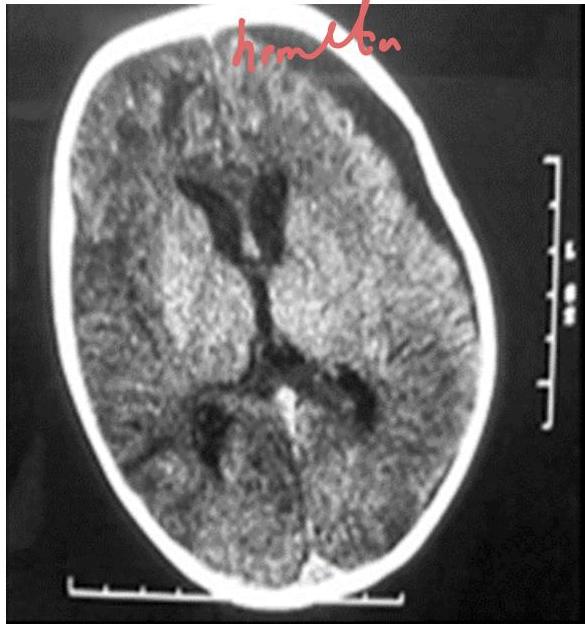

Congenital Toxoplasmosis

This child was delivered with jaundice, HSM, wide spread rashes and progressive head enlarging. Mather gave history of contact with cats early in her pregnancy.

- Diagnosis?

- Congenital Toxoplasmosis “Lipic Vaginal” (Lipic Vaginal), - differential - CMV if paraventricular

Findings:

- Jaundice

- Hepatosplenomegaly

- Widespread rashes

- Progressive head enlargement

- Mother history of contact with cats early in pregnancy

Investigation? Serology (IgM and IgG).

CT Finding: Intracranial calcification (extensive cerebral calcifications) — scattered pattern.

- CNS calcifications (tram calcification pattern)

- Calcification in the border called “tram calcification”

- CMV has calcification around the ventricles (C-shape)

CMV Infection

year old girl has had recurrent episodes of swelling of her hand and feet for last 6 month, these 12 episodes occur following exercise and emotional stress last for 2-3 days and resolve spontaneously. The last episode was accompanied abdominal pain, vomiting and diarrhea the results of routine laboratory workup are normal an older sister and a maternal uncle have had similar episodes as shown in photographs below

Diagnosis? CMV.

CT finding? Periventricular calcification (vs Toxo which is scattered).

- Microcephaly

- Hearing loss

- Non-blanching rash

- Small for gestational age

- Calcification around the ventricles (C-shape)

- History: Mother with mild febrile illness in 1st trimester

Memory aid:

- C-shape calcification = CMV